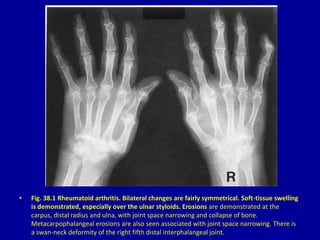

• Fig. 38.1 Rheumatoid arthritis. Bilateral changes are fairly symmetrical. Soft-tissue swelling

is demonstrated, especially over the ulnar styloids. Erosions are demonstrated at the

carpus, distal radius and ulna, with joint space narrowing and collapse of bone.

Metacarpophalangeal erosions are also seen associated with joint space narrowing. There is

a swan-neck deformity of the right fifth distal interphalangeal joint.

• Fig. 38.1Rheumatoid arthritis. Bilateral changes are fairly symmetrical. Soft-tissue swelling is demonstrated, especially over the ulnar styloids. Erosions are demonstrated at the carpus, distal radius and ulna, with joint space narrowing and collapse of bone. Metacarpophalangeal erosions are also seen associated with joint space narrowing. There is a swan-neck deformity of the right fifth distal interphalangeal joint.